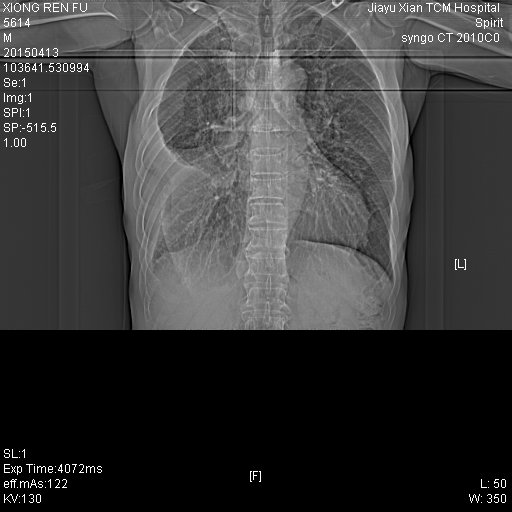

CT50259:男,70Y

各位老师帮看下。咳嗽,四肢无力。

右侧中央型肺癌伴纵隔淋巴转移、胸膜转移

右侧中央型肺癌